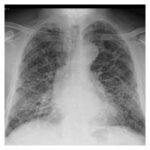

Lung & Kidney Fibrosis

Oxy210 shows promise in cellular models of lung and kidney fibrosis. Through collaborations with outside expert scientists, we are examining the potential of Oxy210 for treating other fibrotic disorders, including idiopathic pulmonary fibrosis (IPF).